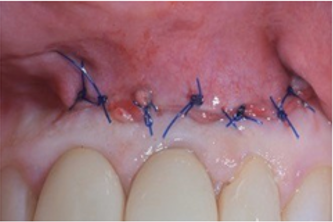

Fig. 9 Wound closure